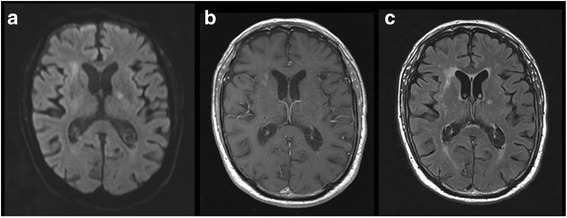

Fig. 3.

Brain magnetic resonance imaging at four weeks of treatment in axial multiple sequences. Decrease of the level of debris layering the occipital horns of the lateral ventricles in all sequences: axial diffusion b1000 (a), axial T1 gadolinium (b) and axial T2 fluid attenuated inversion recovery (FLAIR) gadolinium sequences (c). Clear decrease of the periventricular hyperintensities and ependymal enhancement in T1 with gadolinium (b) and T2 FLAIR gadolinium (c) sequences. Decrease of b1000 DWI hyperintensities. No apparition of new ischemic lesions

Because of this unfavourable outcome, the patient received a prolonged duration of antibiotic therapy, namely cefotaxime for 2 weeks switched to oral levofloxacin (500 mg q 24 h) for another 2-week period. After four weeks of antibiotic treatment, the MRI showed a decrease of the purulent debris inside the ventricles with a clear attenuation of the signal (fig. 3). At that time the patient had regained a normal vigilant status. He only suffered from a cerebellar syndrome with a gait disturbance attributed to ischemic cerebellar lesions. After three months of follow-up, the patient’s condition had improved, allowing him to walk and to return home, even if the help of a wheelchair was sometimes required.